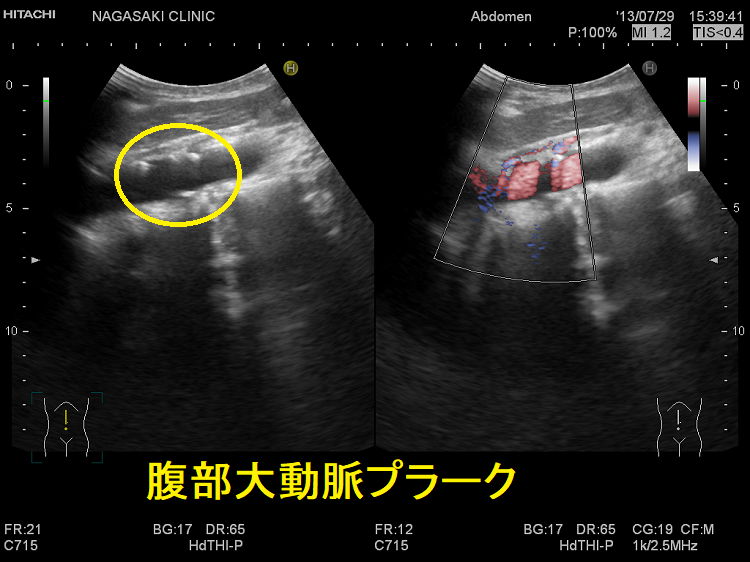

腹部大動脈プラーク

腹部大動脈プラーク;冠状動脈造影検査などの血管内カテーテル操作でプラークが破綻し、飛散したコレステロール結晶が全身の細い動脈に詰まるコレステロール塞栓症を引きおこす可能性があります。

また、血管内カテーテル操作とは無関係に、大動脈粥腫病変は潜因性脳梗塞やEmbolic stroke of undetermined source (ESUS)の塞栓源となり得ます。